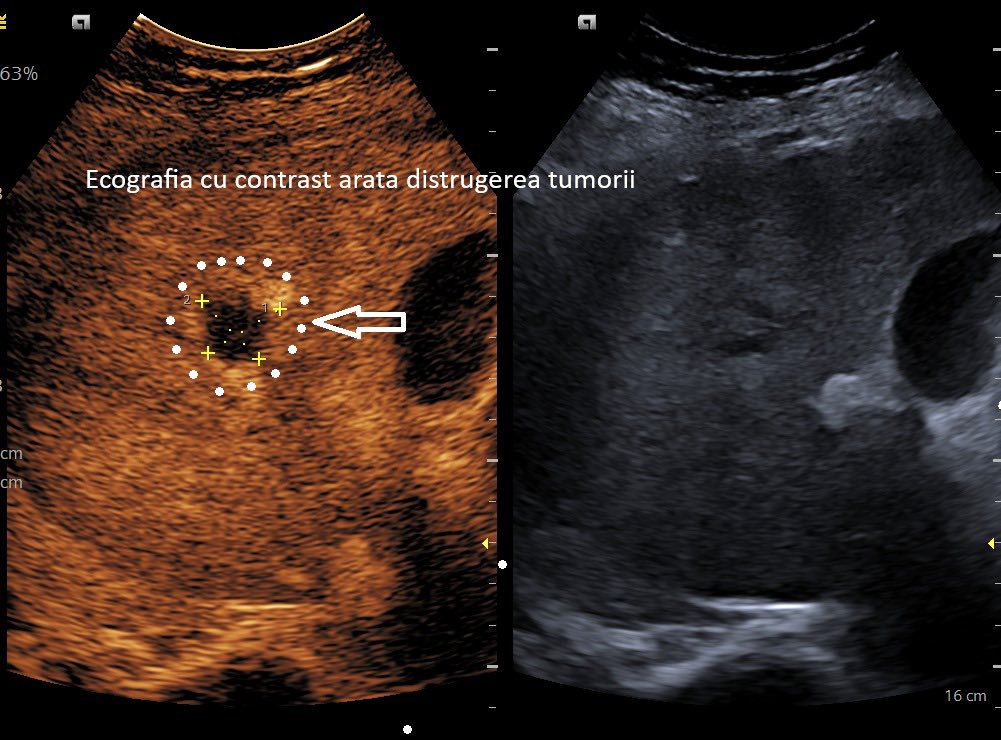

Spitalul Clinic Județean de Urgență Craiova marchează un moment istoric prin realizarea cu succes a unei proceduri minim invazive pentru tratamentul cancerului hepatic. Un pacient a fost tratat fără operație deschisă în Laboratorul de Endoscopie Intervențională al spitalului, iar la o lună post-intervenție, imagistica arată distrugerea completă a tumorii.

Procedura a redus timpul de recuperare și riscul complicațiilor, oferind pacienților o alternativă eficientă la chirurgia tradițională. Această reușită reprezintă un pas important spre medicina de înaltă performanță, orientată pe pacient.